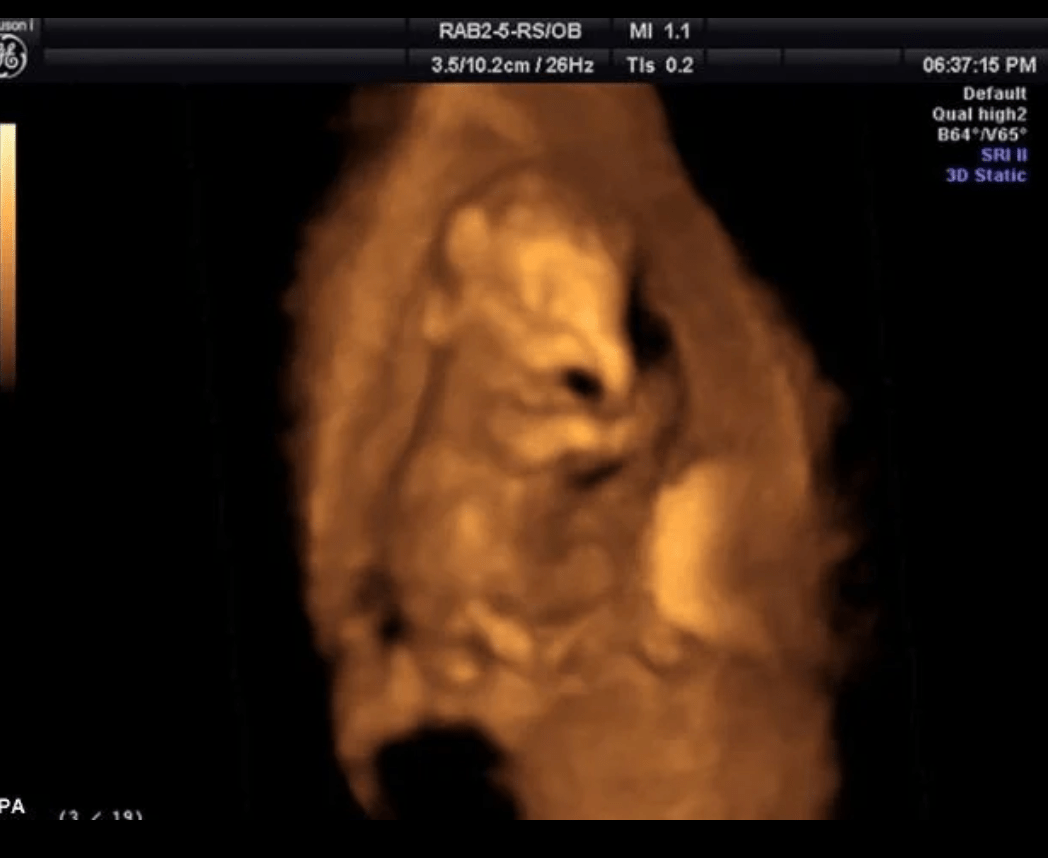

Ultrasound image shows 1 of 5 calves expected to join sedgwick co. Ultrasounds are a regular procedure to check on the elephant’s pregnancy and are conducted by the zoo’s veterinary team. Oct 16, 2024, 08:51 pm. The dominant phyla among baby and adult elephants were bacteroidetes, firmicutes, proteobacteria, kiritimatiellaeota,. Today is samu the baby elephant’s third birthday! “it’s baby season and the little elephants are loyally following after their mothers, for essential milk and protection, as they grow. Zoo elephant herd in 2025. However, we will celebrate him not today, but on saturday, april 27, at 11 a.m. Elephants are pregnant for 21.5 to 22. She is due at the end of this year or beginning of 2025.

Baby Elephant Ultrasound . Elephants are pregnant for 21.5 to 22. Ultrasound image shows 1 of 5 calves expected to join sedgwick co. Today is samu the baby elephant’s third birthday! “it’s baby season and the little elephants are loyally following after their mothers, for essential milk and protection, as they grow. Oct 16, 2024, 08:51 pm. She is due at the end of this year or beginning of 2025. The dominant phyla among baby and adult elephants were bacteroidetes, firmicutes, proteobacteria, kiritimatiellaeota,. However, we will celebrate him not today, but on saturday, april 27, at 11 a.m. Zoo elephant herd in 2025. Ultrasounds are a regular procedure to check on the elephant’s pregnancy and are conducted by the zoo’s veterinary team.